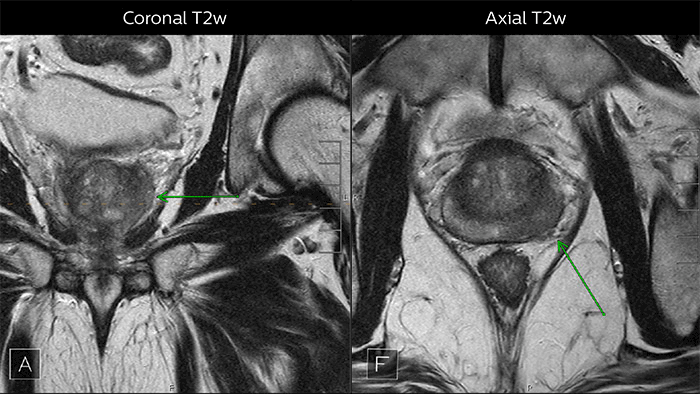

Images from multiparametric MRI of a classic peripheral zone lesion in the prostate

Multiparametric MRI of a classic peripheral zone lesion​

Dr. Steiner describes this case: “For lesions in the peripheral zone of the prostate, the DWI (diffusion weighted imaging) and ADC map are most helpful for diagnosis. In this case, the DWI shows a very bright signal, which indicates diffusion restriction. The arcuate area with significant signal drop out (arrow) on the ADC map is recognized as highly suspect for tumor. On the axial T2-weighted image the capsule contour looks a little irregular (arrow), which we interpret as capsular disruption, and I usually give a measurement: this lesion shows larger than 1.5 cm capsular disruption. I don’t see any signs of lymphadenopathy, but interpret this lesion as PI-RADS 5. The hypervascular flow pattern in the bottom images adds to the diagnostic confidence.” ​